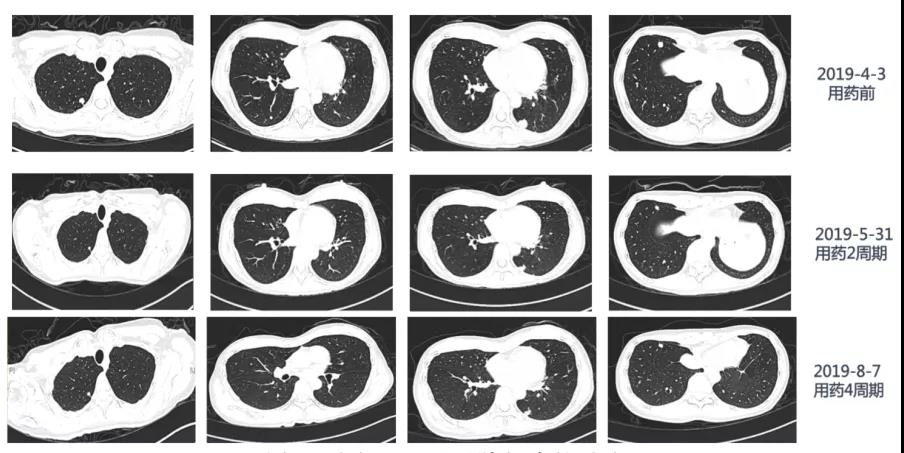

于2019年4月5日给予呋喹替尼5mg d1~21,每28天1个周期,共4周期。患者耐受良好,1级口腔黏膜炎,无高血压、蛋白尿、手足皮肤反应、肝肾功能异常等不良反应。2周期复查:CEA下降至17.4 ng/ml,胸部CT示肺转移灶较前明显缩小,疗效评价部分缓解(PR)。4周期复查:CEA降至11.8 ng/ml,胸部CT 较前无显著改变,疗效评价为维持PR(图5)。

本例患者前线使用贝伐珠单抗,疾病进展后更换为呋喹替尼仍表现出良好的抗肿瘤作用,使用呋喹替尼2周期后,患者CT评价肺部转移灶达到PR,另外CEA下降明显,提示疾病得到控制,并且除1级口腔黏膜炎外,无高血压、蛋白尿、手足皮肤反应、肝肾功能异常等不良反应,患者生活质量也得以保证。